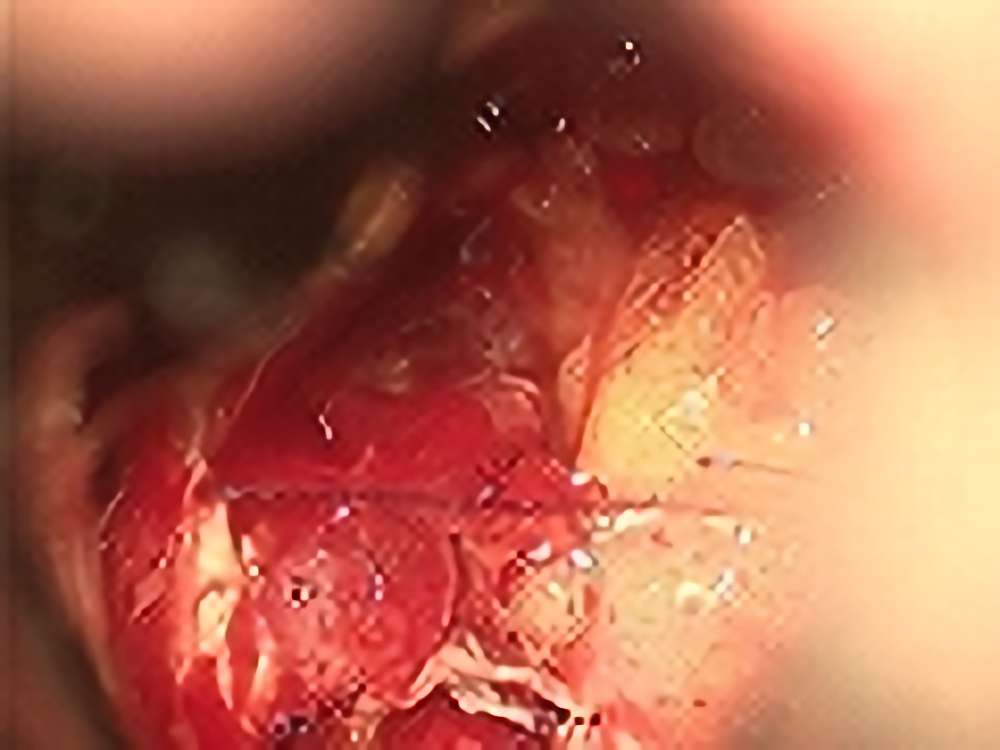

頭頂葉海綿状血管腫

No.’13_169 手術前1

No.’13_169 摘出 前

No.’13_169 摘出 後